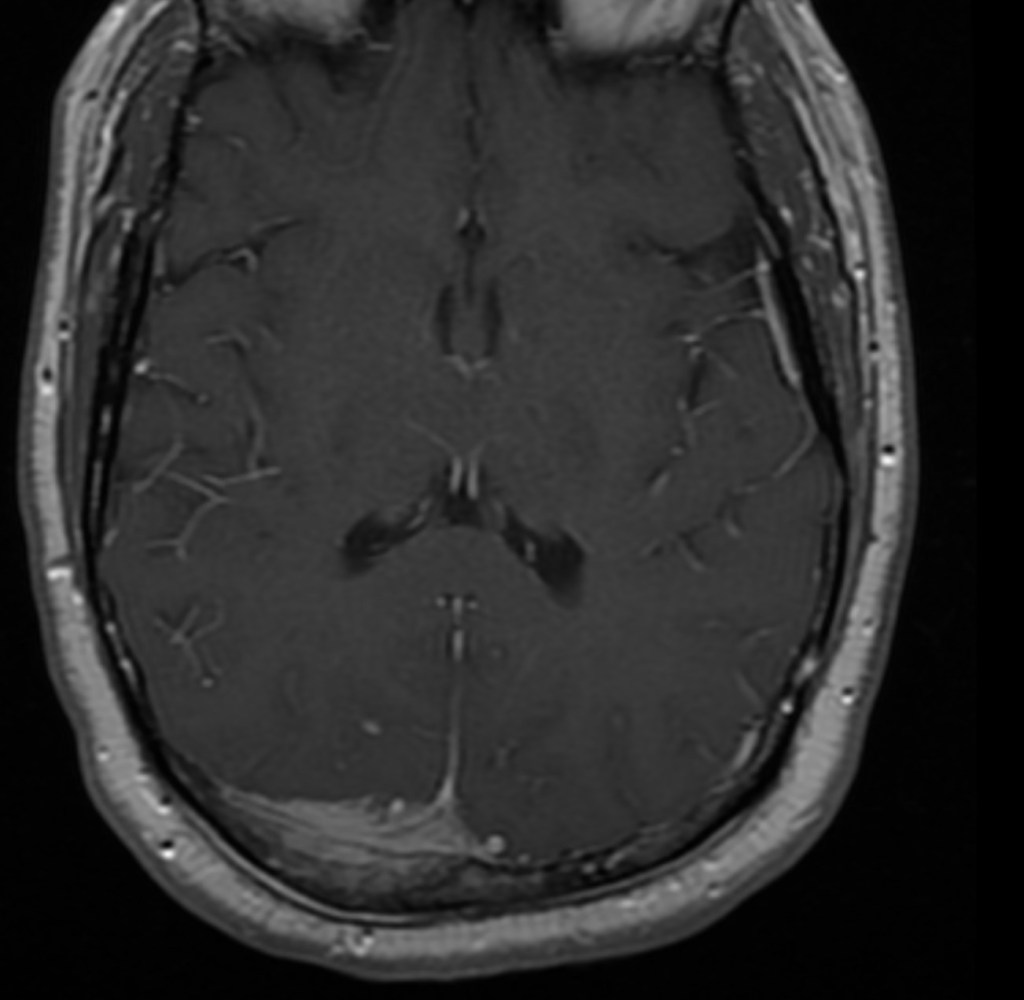

To remind everyone about the size and location of the tumor

The tumor from the above view